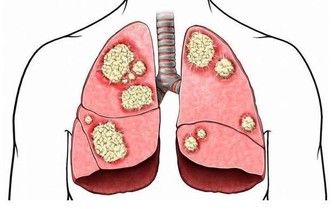

人每天進行呼吸,通過呼吸攝取氧氣,而氧氣必須抵達身體各個角落才能發揮其用處。而氧氣運輸至各個地方,這就離不開血管,需要血管來做“載體”,承載著氧氣及各類營養物質,一直傳送到各個器官內臟,從而促進身體各項機能的正常作用,以此來構建一個健康的身體。

如果血管發生堵塞,或者血管異常窄,那麼氧氣的運輸以及物質循環就會被影響,甚至受到阻礙,那麼身體需要氧氣的各個器官組織也會出現異常,功能不能正常實現,身體的健康受到危害,嚴重的話會引發更多的心腦血管疾病,危及生命。